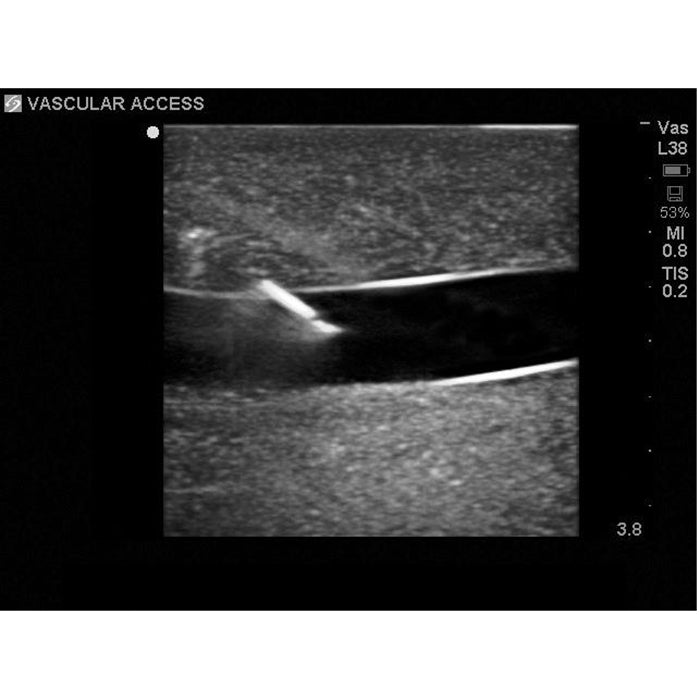

sternal notch. Users can utilize traditional anatomical landmarks for blind insertion techniques, or utilize ultrasound

Brand New! 2nd Generation upper torso ultrasound guided central line placement training model with transparent tissue insert allows users to develop and practice the skills necessary to gain proficiency in using ultrasound to guide central catheter insertions in the internal jugular vein (IJ), subclavian vein, and axillary vein while revealing the venous and arterial vessels as well as accessory boney structures. Developed with the goal of helping clinicians bridge the learning gap by allowing them to see the internal anatomical structures with their eyes as well as with ultrasound imaging, our transparent central line placement tissue offers superb ultrasound hands-on training. Using Blue Phantom proprietary simulated human tissue, this very realistic and ultra-durable transparent central venous access ultrasound training model is excellent for training clinicians in the psychomotor skills associated with ultrasound guided central line placement procedures. These ultrasound imaging skills include; using ultrasound system controls, transducer positioning and movement, recognition of arterial and venous anatomy, using ultrasound to target the appropriate vessels for cannulation, and performing a central venous access procedure.Helps

- Superb ultrasound imaging characteristics

- Accommodates full threading of guidewires and catheters

- Positive fluid flow in the vessels provides users with immediate feedback when vessels are accessed

- Tissues match the acoustic characteristics of real human tissue so when you use your ultrasound system on our training models, you experience the same quality you expect from imaging patients in a clinical environment

- Superb ultrasound imaging characteristics

- Positive fluid flow in the vessels provides users with immediate feedback when vessels are accessed

- Tissues match the acoustic characteristics of real human tissue so when you use your ultrasound system on our training models, you experience the same quality you expect from imaging patients in a clinical environment